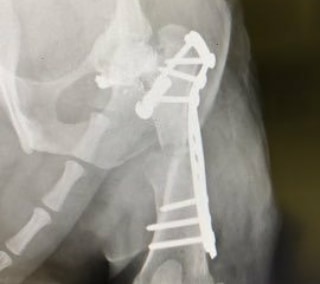

Diagnoza: hud zlom stegnenice, dislokacija pogačice, omejena gibljivost kolka

Prognoza: 2 operaciji, eno je že prestal, naravnali smo stegnenico, druga ga še čaka – poravnava pogačice, odrstranitev zgornjega dela stegnenice, da se povrne gibljivost kolka in odstranitev metka.